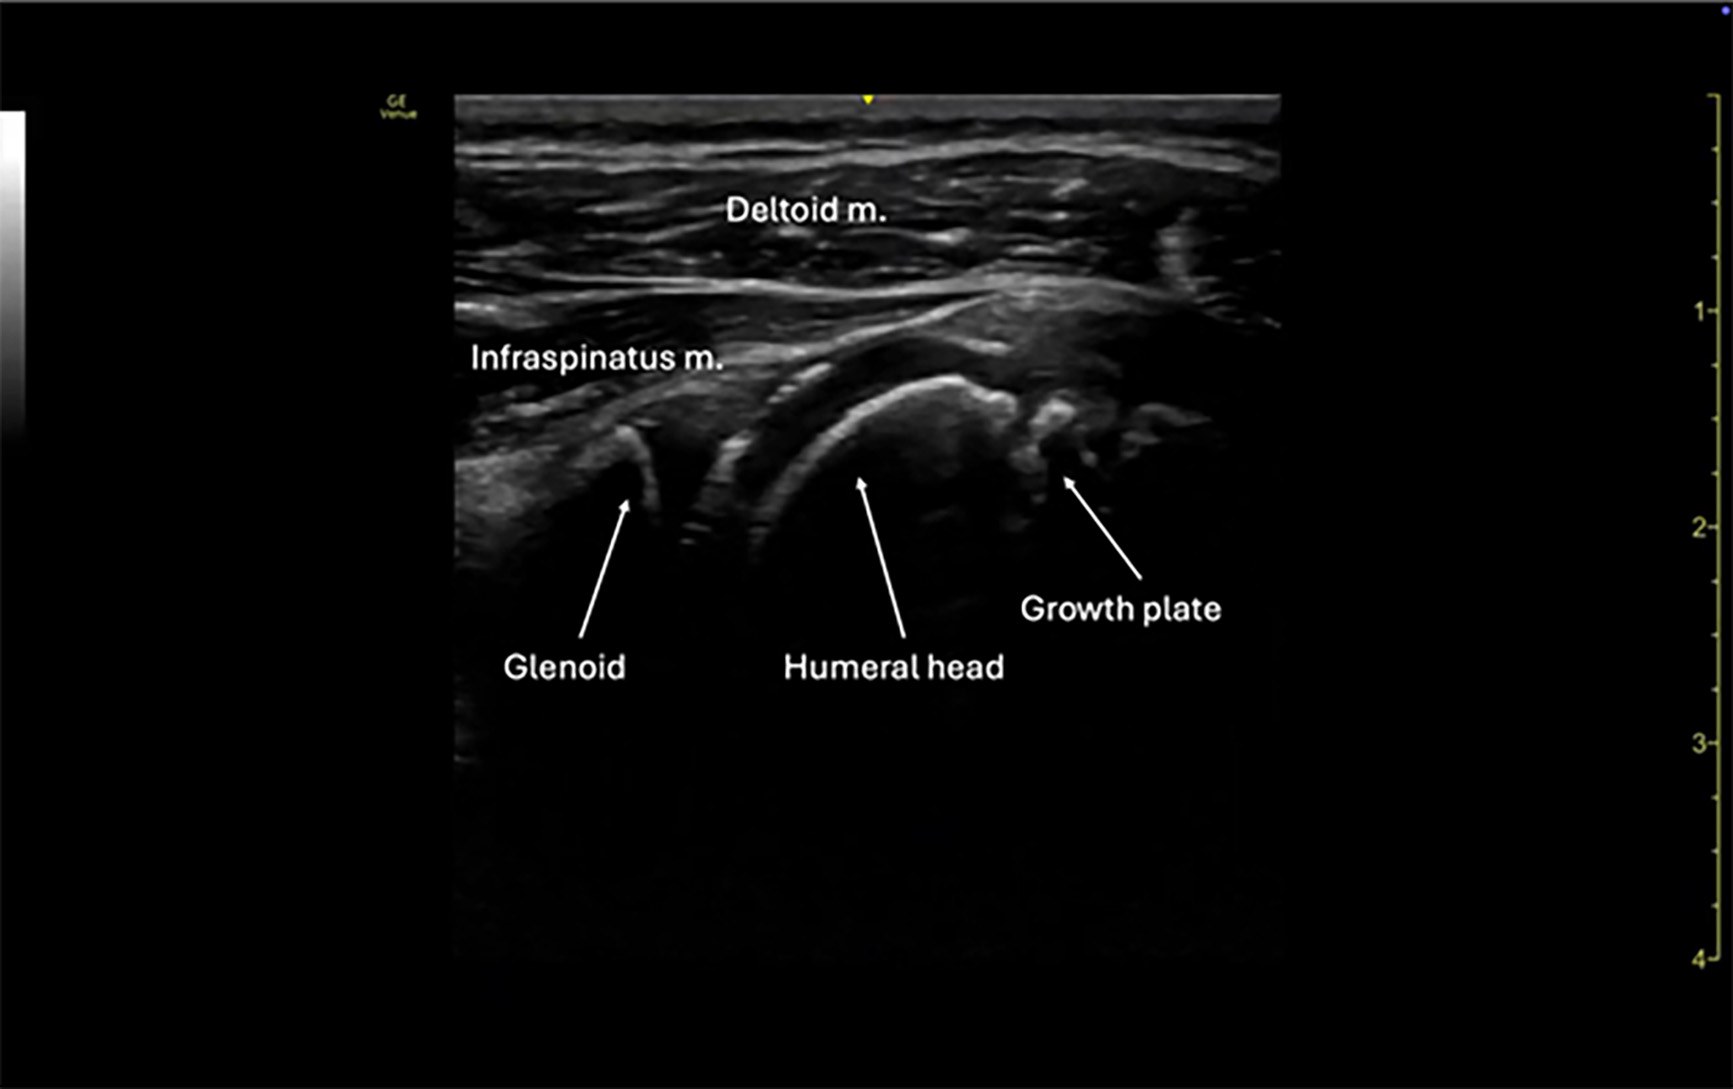

The posterior approach to shoulder ultrasound is the preferred technique for evaluating suspected dislocations. With the patient seated or in the lateral decubitus position, place a high-frequency linear probe transversely on the posterior aspect of the shoulder, just inferior to the scapular spine. The probe marker should point laterally. Identify the glenoid fossa and humeral head. In a normal (reduced) shoulder, the humeral head will sit congruently within the glenoid. (See Figures 6 and 7.) In an anterior dislocation, the humeral head will appear displaced anteriorly (and thus deeper on the screen), while in a posterior dislocation it will lie posteriorly and more superficial.

Figure 6. Normal Shoulder View |

3-year-old male via linear probe |

![]() |

Image courtesy of: Matthew D. Holmes, MD. |

Figure 7. Normal Shoulder View |

5-year-old female via linear probe |